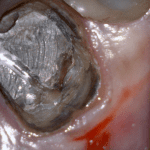

This case was scanned by two different scanners. Once by the Medit i500 and another time with the Aoralscan. Both the meshes are included so you can compare the two. It was scanned to deliver a case that retrofits a partial denture